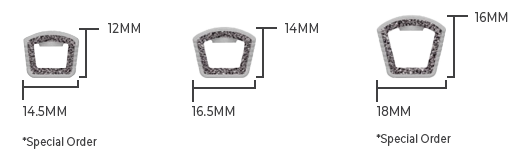

Width/Length Options